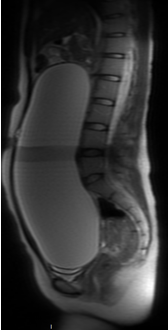

医生给**女士进一步完善了妇科超声,提示腹盆腔巨大囊性包块,范围广无法测量,上至剑突下,下至盆腔,边界不清,盆腔及腹部磁共振也提示,腹盆腔内巨大占位性病变,考虑来源于右侧卵巢,卵巢囊腺瘤可能性大。

盆腔及腹部磁共振提示,腹盆腔内巨大占位性病变